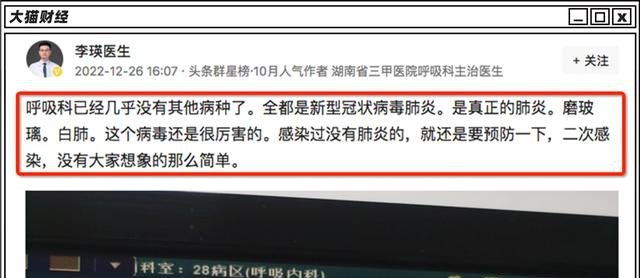

一线医生说,目前的呼吸科基本上全是肺炎患者,“真正的肺炎,磨玻璃,白肺”。

一线医生认为,过于乐观的情绪,导致了不少人对奥密克戎的轻视。

武汉大学人民医院呼吸内科主任余昌平认为,奥密克戎引起肺炎的概率减少,但是因为感染基数太大,导致的肺炎人数还是不少的,“引起的肺炎远高于流感”。

“奥密克戎造成的总死亡人数不容忽视,各个医院呼吸科感染科医生都很清楚,奥密克戎引起的病毒性肺炎也非常多,有的病情还非常严重。”